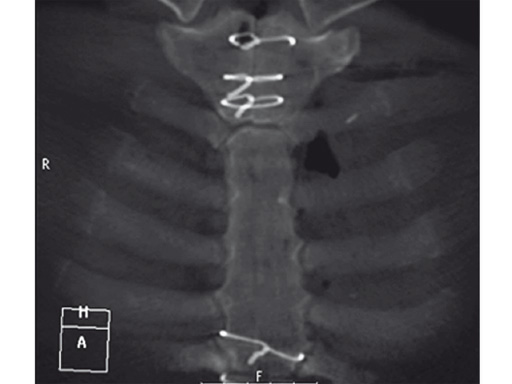

Case 2: A 55-year-old woman, who previously underwent ventricular septal defect closure at 5 and aortic valve reconstruction at 31, required aortic valve replacement due to symptomatic aortic valve insufficiency.

The patient was morbidly obese with a BMI of 45. Due to the high risk for sternal instability and/or deep sternal wound infection, closure was performed using the sternal zipfix system. The zipfix provides quick and reliable stable fixation of the sternum even in patients that are at a higher risk to develop a sternal instability or a deep sternal wound infection.

The postoperative course was uneventful and the patient was discharged on postoperative day 7 with no signs of sternal instability or wound healing problems. At 18 months follow-up the wound had healed completely and the sternum was stable, with no signs of infection.